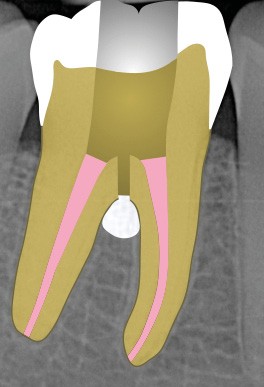

Perforation supra-osseuse (fig. 1)

Les perforations supra-crestales sont la plupart du temps iatrogéniques et surviennent lors de la réalisation de la cavité d’accès, ou de la recherche des entrées canalaires. Il s’agit généralement d’une communication avec un diamètre bien défini et aux contours nets. De ce fait, ce type de perforation est appelée « perforation à quatre parois ». Les perforations peuvent également être d’origine pathologique (résorption cervicale externe, carie active).